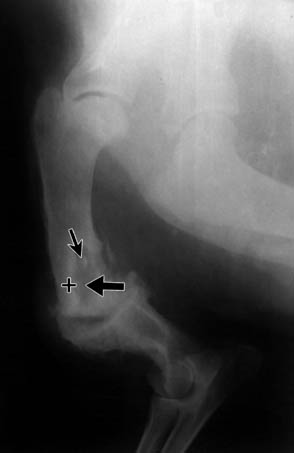

Fig. 4. Anterior-posterior radiograph of the tibia in patient 26/16.09.92, four weeks after osteosynthesis. The arrows show a zone of radiolucency around the screws - a sign of screw loosening.

Fig. 5. Lateral radiograph of the femur in patient 27/13.01.93. Thin arrows show a Brodie's abscess; the cross (+) - osteosclerosis surrounding the abscess; the thick arrows - sunburst-like formations of the periosteum.

During that period, in 3 dogs (13%), a Brodie's abscess was formed - zones of radiolucency (osteolysis) with a round or irregular shape, surrounded by a denser ring (osteosclerosis). This radiological sign was characteristic of inflammations in the metaphyses of long bones (Fig. 5).

By the end of week 8, sequestra formed in another 4 dogs (18%). The most frequently occurring sign was the formation of a sclerotic buttress around already formed and newly formed sequestra - 14 or 64%. In the same period, a further three cases with Brodie's abscess appeared.

An important radiological feature is the Brodie's abscess. It was present in only 14% of the cases we studied. It is characterized by a round shape without sequestrum, with smooth, well-defined contours. It is localized within the sclerotic cancellous tissue in the metaphyses of long bones.